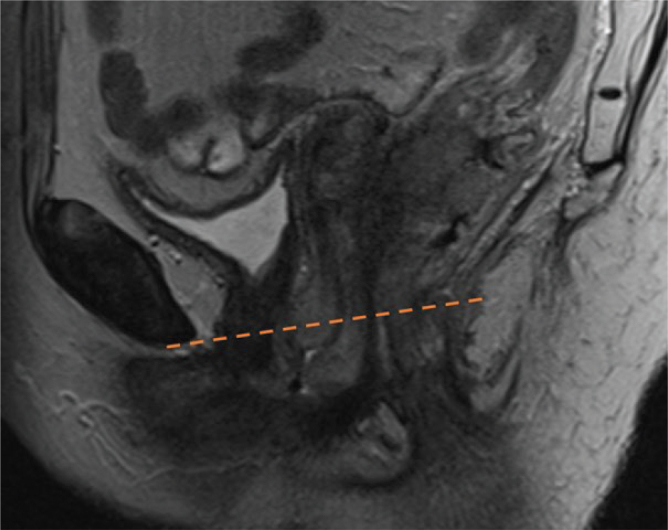

Results: Applying the risk-adapted alternative of the NOAC guidelines had the external iliac region omitted in 41.0% of the patients. The cranial border was lowered from the common iliac bifurcation in 27.7% and elevated in 12.7% of the patients. Elderly patients (≥70 years) more often had the external iliac region omitted than younger patients (60.9% vs. 33.3%; p = 0.001). The entire ischiorectal fossa was included in 23.7% of the patients due to tumor extension beyond the levator ani muscles or external sphincter.

Interpretation: Contouring according to the NOAC risk-adapted guidelines changed, and mainly reduced, the CTVe in about half of all patients. Prospective follow-up is needed to determine if this is clinically beneficial.